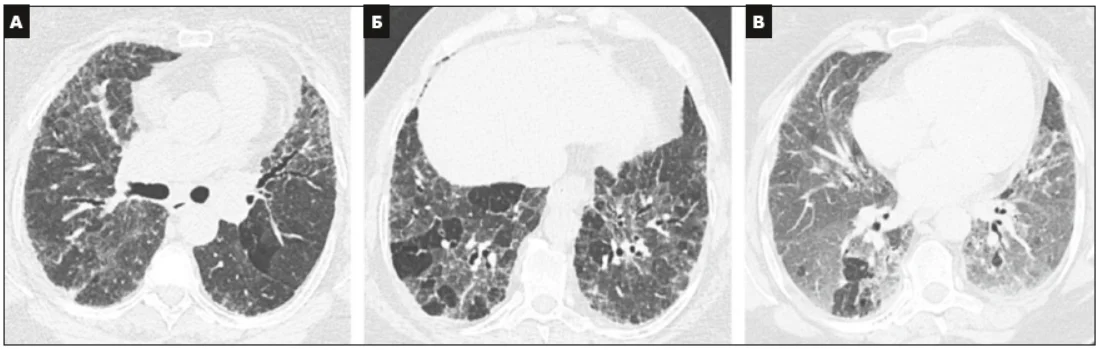

Виділено 4 діагностичні категорії, які складаються з КТ-симптомів (табл. 2 доповнена у 2022 р.). Ці категорії охоплюють ЗІП-патерн (рис. 1), імовірний ЗІП-патерн (рис. 2), невизначений (сумнівний) ЗІП-патерн (рис. 3) і альтернативний діагноз (рис. 4).

Рис. 4. КТВРЗ-патерн, який дає підстави для альтернативного діагнозу.

Поперечні зрізи КТ (А і Б), отримані на глибокому вдиху, показують дисеміновану інфільтрацію легень, зберігаються деякі вторинні легеневі часточки в базальних відділах легень. Поперечний зріз КT, отриманий на видиху (В), підтверджує часткову повітряну пастку. Усі дані свідчать про хронічний гіперсенситивний пневмоніт [31].